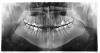

igore Опубликовано 20 октября, 2010 Поделиться Опубликовано 20 октября, 2010 много лет страдаю заболеваниями носоглотки. при любом переохлаждении воспаляются пазухи, ноющие давящие боли. поднимается температура. перегородка не искривлена. делал посев из носа, находили стафилококк, лечился антибиотками, не помогло.на днях сделал панарамную томограмму, в надежде что выяснится причина постоянных мучений.посмотрите пожалуйста снимок Ссылка на комментарий

pawa Опубликовано 20 октября, 2010 Поделиться Опубликовано 20 октября, 2010 Панорамный снимок не самый лучший вариант для диагностики пазух. По этому снимку смотрят зубы и челюсти. Ссылка на комментарий

Scrabble Опубликовано 20 октября, 2010 Поделиться Опубликовано 20 октября, 2010 много лет страдаю заболеваниями носоглотки. при любом переохлаждении воспаляются пазухи, ноющие давящие боли. поднимается температура. перегородка не искривлена. делал посев из носа, находили стафилококк, лечился антибиотками, не помогло.на днях сделал панарамную томограмму, в надежде что выяснится причина постоянных мучений.посмотрите пожалуйста снимокЕсть изменения в синусе справа. Причина не в зубах. Ссылка на комментарий